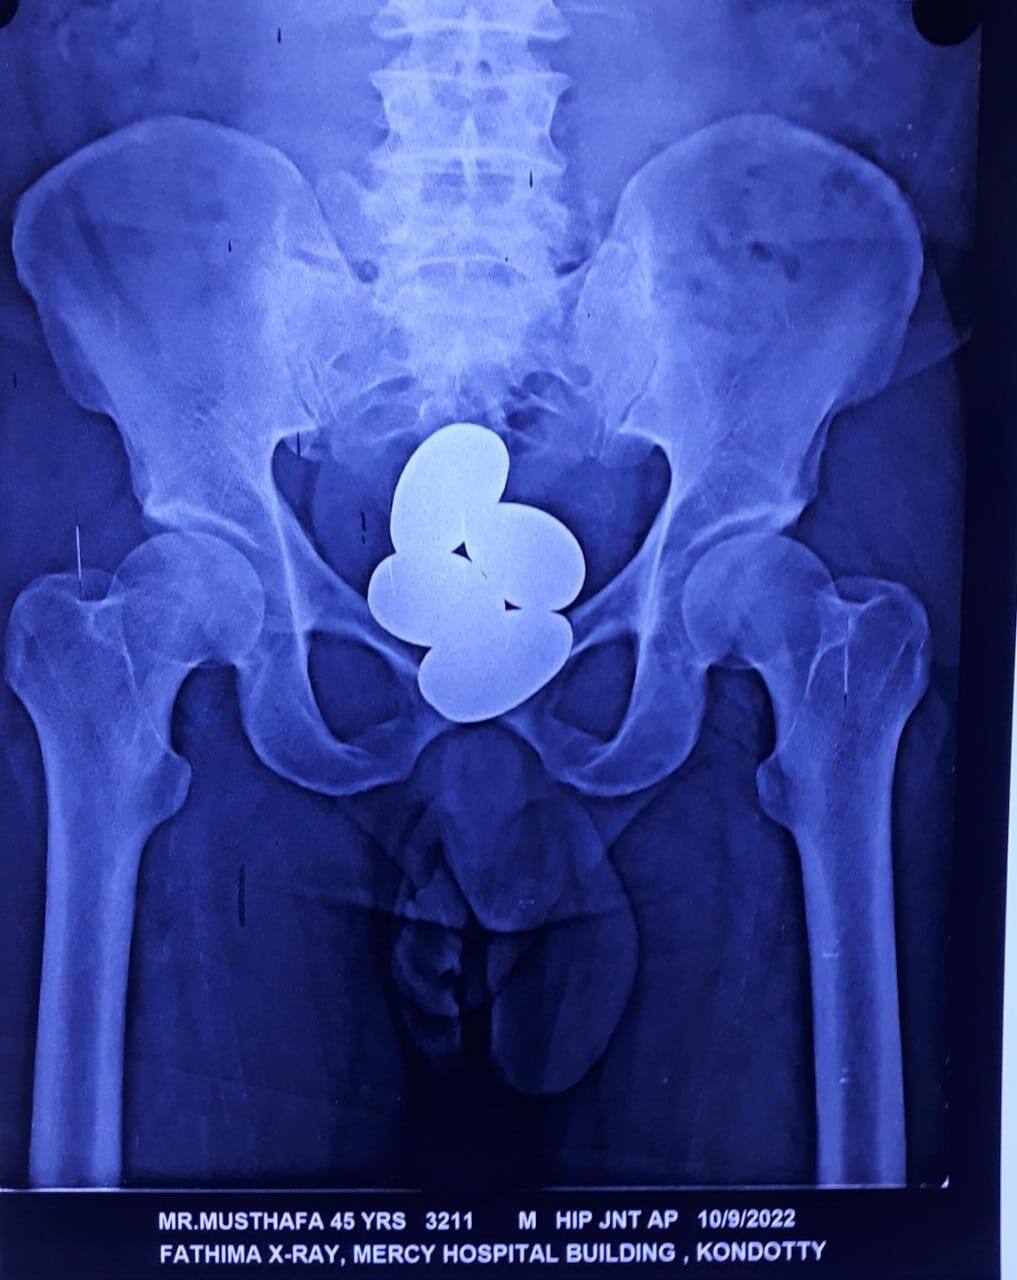

മലപ്പുറം: കരിപ്പൂരിൽ വീണ്ടും പോലീസിൻ്റെ സ്വർണ വേട്ട. കുഴിമണ്ണ സ്വദേശി മുസ്തഫ (41) ആണ് ഇത്തവണ പിടിയിലായത്. 992 ഗ്രാം മിശ്രിത രൂപത്തിൽ ഉള്ള സ്വര്ണമാണ് ഇയാൾ മലദ്വാരത്തിൽ നാല് ക്യാപ്സൂളുകളിലായി നിറച്ച് ഒളിപ്പിച്ച് കടത്താൻ ശ്രമിച്ചത്. ശനിയാഴ്ച രാവിലെ 11.15 മണിക്കാണ് മലപ്പുറം കുഴിമണ്ണ സ്വദേശി മുസ്തഫ ജിദ്ദയില് നിന്നും കരിപ്പൂര് എയര്പോര്ട്ടില് വന്നിറങ്ങിയത്.

തുടര്ന്ന് മുസ്തഫയെ കൊണ്ടോട്ടിയിലുള്ള മേഴ്സി ആശുപത്രിയില് എത്തിക്കുക ആയിരുന്നു. മെഡിക്കല് ഓഫീസറുടെ നിര്ദേശാനുസരണം എക്സ്റേ എടുത്ത് പരിശോധിച്ചതോടെ തൊണ്ടി സഹിതം വ്യക്തമായി. വയറിനകത്ത് സ്വര്ണ്ണമടങ്ങിയ 4 കാപ്സ്യൂളുകള് ആണ് എക്സ് റേയിൽ തെളിഞ്ഞത്. ഇയാളില് നിന്നും പിടിച്ചെടുത്ത സ്വര്ണ്ണത്തിന് 992 ഗ്രാം തൂക്കമുണ്ട് (ഏകദേശം 124 പവൻ).